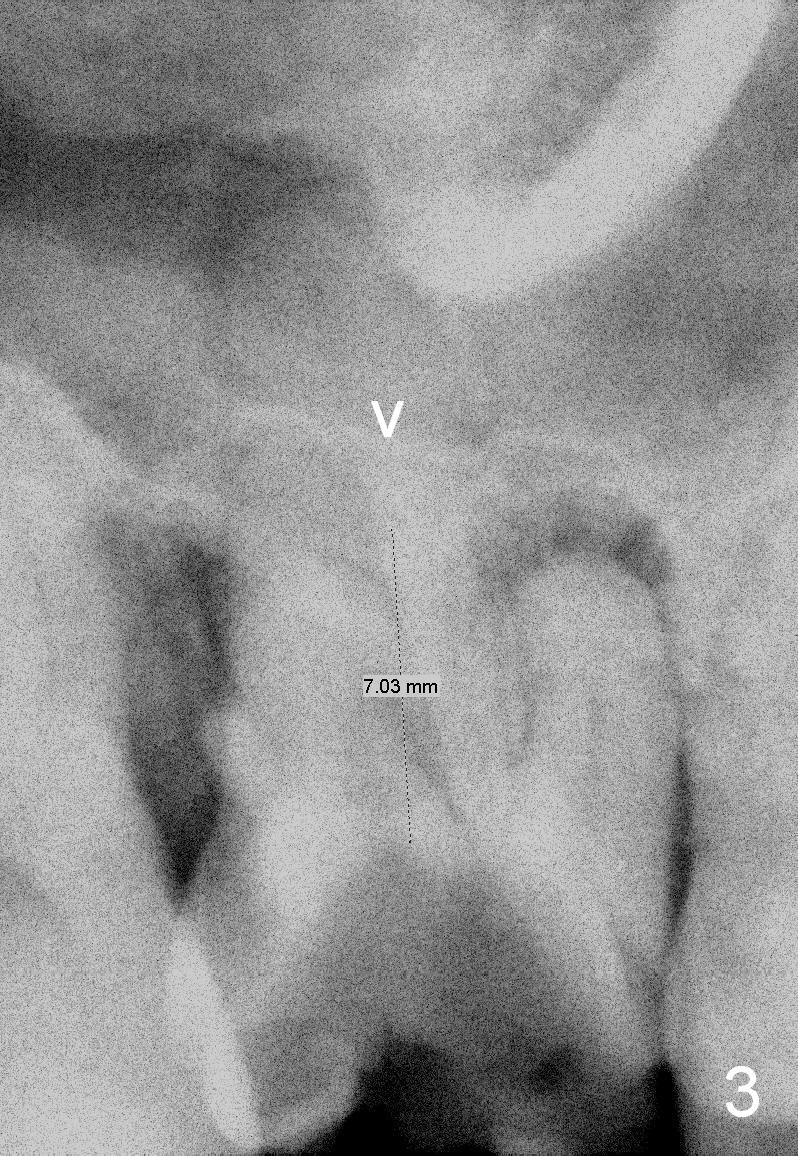

A 43-year-old man will return for #3 implant placement, 2.5 years after extraction. Pre-extraction PAs (Fig.1,2, taken 5 and 2.5 years ago) show that the palatal apex (Fig.1 P) is much higher than the buccal ones (*). The tooth became non-salvageable because of caries (Fig.2 C) in 2.5 years with periapical radiolucency (*). After extraction, the bone available for implantation is probably below the sinus floor (Fig.1,3 arrowheads), 7-9 mm.